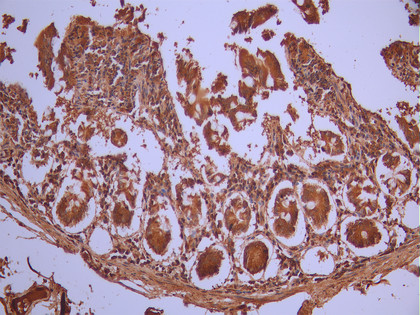

• IHC image of CSB-RA091918A0HU diluted at 1:100 and staining in paraffin-embedded human small intestine tissue performed on a Leica BondTM system. After dewaxing and hydration, antigen retrieval was mediated by high pressure in a citrate buffer (pH 6.0). Section was blocked with 10% normal goat serum 30min at RT. Then primary antibody (1% BSA) was incubated at 4°C overnight. The primary is detected by a Goat anti-rabbit polymer IgG labeled by HRP and visualized using 0.05% DAB.